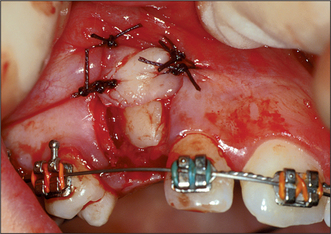

3. In Fig. 12.18 the upper right canine tooth has been surgically exposed.

(a) Describe the type of flap that has been used.

(b) Why has the excess tissue not been surgically excised at the same time?

(c) What other technique can be used to prevent the defect healing?

(d) What else could be done at the time of surgery to encourage eruption of the tooth?

image

Fig. 12.18 See question 3.